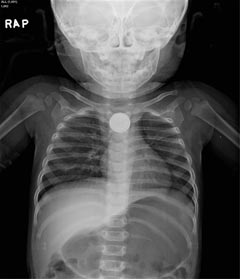

단추형 전지를 삼키면 몸 안에서 누전돼 조직에 전기적인 화상을 입히게 된다. 식도나 위장관에 들어가면 화학반응을 일으켜 성대와 식도, 혈관 등에 손상을 줄 수 있다. 특히 식도에 걸렸을 경우에는 누전에 의한 손상 뿐 아니라 식도 벽이 전지에 의해 눌려 압력괴사까지 발생할 수 있다. 조기에 제거하면 별 탈 없이 회복하지만 시간이 늦어지면 식도 등 장기에 천공을 유발하고 심각한 경우 대동맥 손상으로 사망에 이르기까지 한다.

세브란스 어린이병원 소아외과 한석주 교수는 “삼킨 후 늦어도 4시간 이내에 전지를 제거하지 않으면 식도 손상이나 천공 혹은 대동맥 파열 등 심각한 합병증을 유발할 수 있다”며 “단추형 전지는 크기가 작아 아이들이 먹어도 부모들이 모르는 경우가 대부분이어서 항상 관리에 조심해야 하며, 만약 전지를 삼킨 아이가 통증이나 기침, 구토 등의 증상을 보일 경우 바로 응급실을 찾는 것이 좋다”고 말했다.